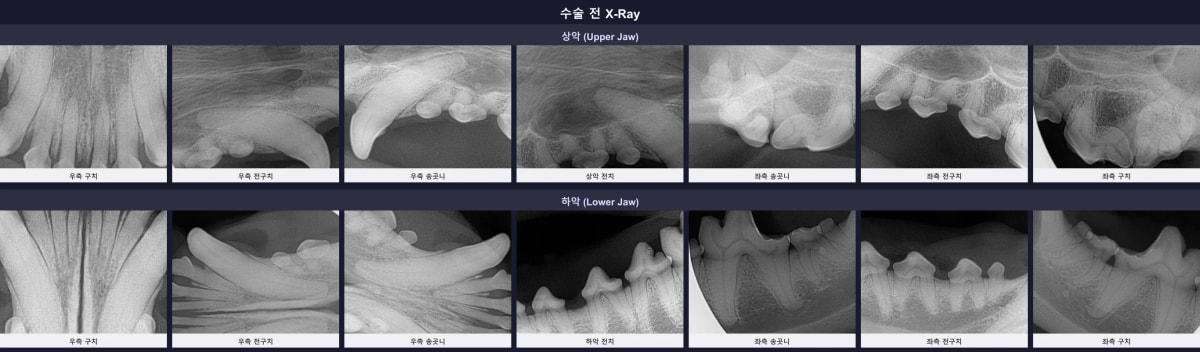

3. 수술 전 구강 엑스레이 (방사선) 검사 소견

CT 검사와 더불어 수술 전 구강 방사선(X-ray) 촬영을 진행하여 각 치아의 상태를 세밀하게 분석했습니다.

수술 전 구강 엑스레이 소견: 치조골 흡수 및 법랑질 손상 부위 확인

엑스레이 결과, 다행히 육안상 문제가 보였던 우측 위쪽 어금니(109번) 외에는 턱뼈를 위협할 만한 치명적인 손상은 없었습니다. 하지만 나이로 인해 108, 208, 209, 309, 409번 등 여러 치아의 법랑질(치아 겉면)이 깨져 변색(EF)되어 있었고, 209, 301, 401번 치아 주변으로는 치조골 흡수(ABL2 단계)가 관찰되었습니다. 잇몸 부종과 약한 치아 흔들림이 동반된 상태였습니다.